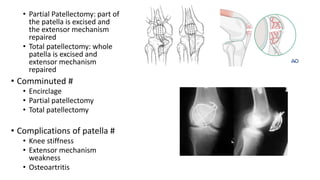

• Partial Patellectomy: part of

the patella is excised and

the extensor mechanism

repaired

• Total patellectomy: whole

patella is excised and

extensor mechanism

• Comminuted #

• Encirclage

• Partial patellectomy

• Total patellectomy

• Complications of patella #

• Knee stiffness

• Extensor mechanism

weakness

• Osteoartritis